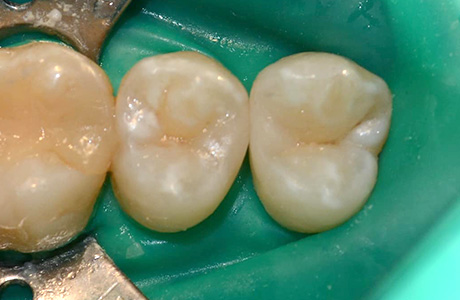

До и после лечения

В нашу клинику обратилась пациентка, которую беспокоили болевые ощущения слева сверху во время приёма сладкой или кислой пищи. В процессе осмотра и диагностики было установлено, что причиной болей и дискомфорта является хронический средний кариес 14, 15 зубов.

Процесс работы

Ход работы:

- применение инфильтрационной анестезии;

- механическая обработка кариозной полости с использованием коффердама;

- пломбирование светокомпозитным материалом;

- микроконтурирование и макроконтурирование пломбы.